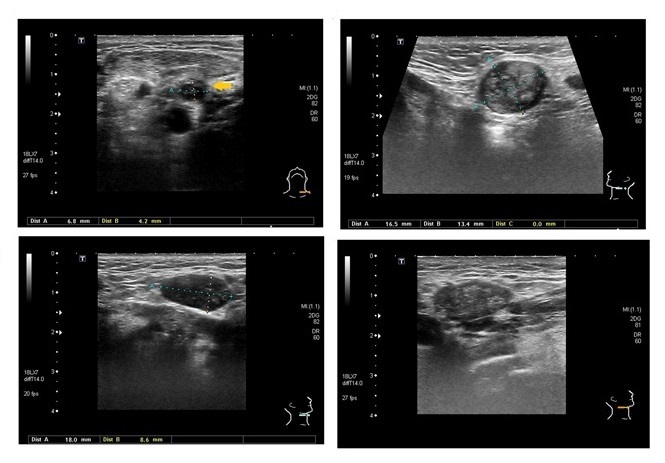

February 13th 2014. Thursday morning and I went straight to the doctors, unfortunately I had to wait nearly an hour as the doctor was very busy, my own doctor was off sick and there was a replacement doctor working. When I got to see her she asked what was wrong and I said three things, 1. I have an annoying cough that will not go away, 2. I have black floaters in my right eye that seem to have got worse in the past 24 hours and 3. The right side of my neck is swollen. Number three seemed too had got her attention, she examined my neck and without a word left the room. The doctor returned a few minutes later and asked if I felt okay to drive, I said yes and asked why. The doctor advised me that she had just phoned the hospital and had organised for an ultra sound to be done to the neck. I have private health insurance called VHI. The doctor said that they would look at the other issues but classed the swollen neck as urgent. I called in home and asked Anita to drive me to the hospital. Arriving into the hospital I was expecting to be delayed but to my surprise I was taken immediately, this was the first time that I actually felt concerned it was too quick. The nurse doing the ultrasound also looked concerned and went to get the radiologist, he spent about 20 minutes performing more ultrasounds on me, he then asked me to wait in the waiting room. I had just taken a seat beside Anita when we both notice the radiologist running down the corridor, I recall saying to Anita “Hope that’s not about me” and we both laughed. But the laughter didn’t last long. The Radiologist returned a few minutes later and came straight over to us, he explained that he had dashed out to try and get a surgeon but missed him. He told me to head home and wait for a call from the surgeon. We headed home thinking this may not be really that big a deal after all. I got a call an hour later that changed that. The hospital wanted me in at 9am the next day for a “small surgical procedure”.